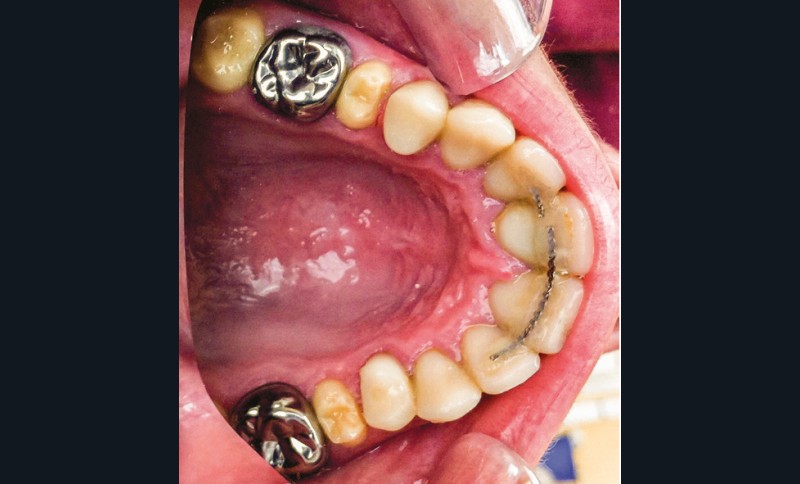

Une patiente âgée de 12 ans a été adressée au cabinet pour « une prise en charge complète sur le long terme » par son praticien traitant. Elle était accompagnée par sa mère. Elle présentait des couronnes transitoires en résine sur le secteur incisivo-canin au maxillaire ainsi que les premières prémolaires, des coiffes pédodontiques métalliques sur les premières molaires, une absence totale d’émail sur l’ensemble de la denture, à l’exclusion des bords libres des incisives mandibulaires (fig. 1 à 3). Le bloc incisivo-canin mandibulaire avait bénéficié de traitements radiculaires (fig. 4). Les incisives maxillaires présentaient des rhizalyses d’une importance significative (fig. 5 et 6). La patiente se plaignait d’hypersensibilités à la mastication et au brossage, la demande esthétique était forte.